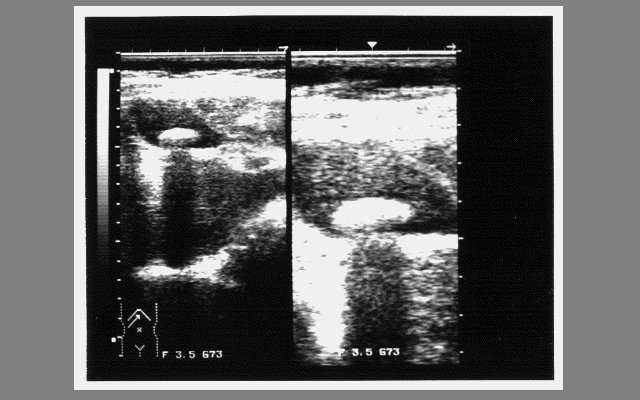

その次は、当院の胆石症の患者の腹部エコー像である。モノクロ16階調ではかなり細かいニュアンスまでが表示できることを見ていただいた。最後は、同じ画像のパレットを変えるとこのような奇怪な画像に変わることを供覧し、16色ではパレットファイルが本体と同じほど重要であることを強調した。